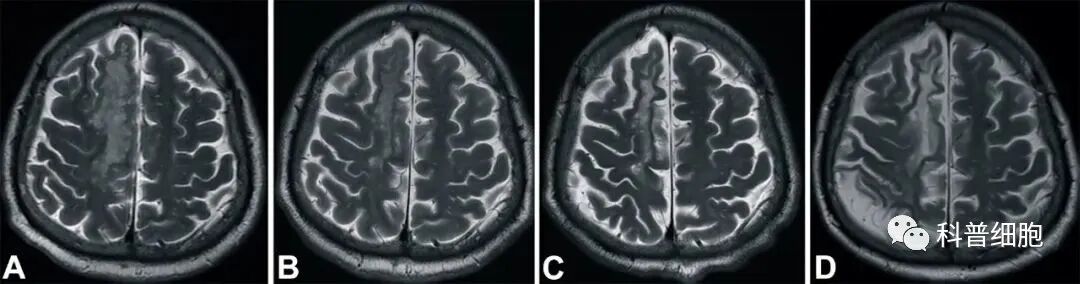

近日,中国台湾花莲慈济大学医学院报道了一个案例:一名缺血性脑卒中偏瘫患者在治疗后12个月内取得完全康复,结果发表在Cell Transplantation(细胞移植)期刊上。

结果表明,接受 HLA6/6匹配的脐静脉血液来源的单个核细胞输注之后,这名缺血性卒中成年患者在短时间内明显康复。

脐带来源的干细胞已经被证明在中风急性期和亚急性期的动物模型中,能发挥强大的治疗作用。除了再生能力以外,这些细胞还具有免疫调节和抗炎作用。因此,它们可以保护脑组织免受中风后炎症引起的继发性损伤。这项研究还使用了甘露醇,帮助干细胞更好的穿透血脑屏障,增强神经营养因子和神经生长因子的表达。

这一案例中,患者的康复令人印象深刻,可能与中风后第8天就接受治疗有关。我们期待更多相关研究的积极结果,特别是大规模临床试验。